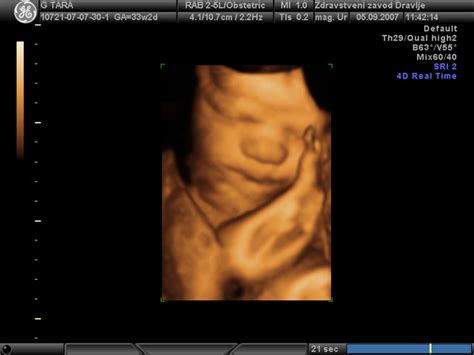

Poleg gibanja, otrok v materinem trebuhu razvija tudi druge sposobnosti. Britanski znanstveniki so z opazovanjem 4D ultrazvočnih slik ugotovili, da se plod v 24. tednu starosti že lahko smeje, pri 36. tednu pa se lahko izraža skozi različne obrazne kretnje, od spusta obrvi do namrščenega noska in širokega nasmeha. Dojenčki v maminem trebuhu pogosto sesajo svoj prst in tudi zehajo.